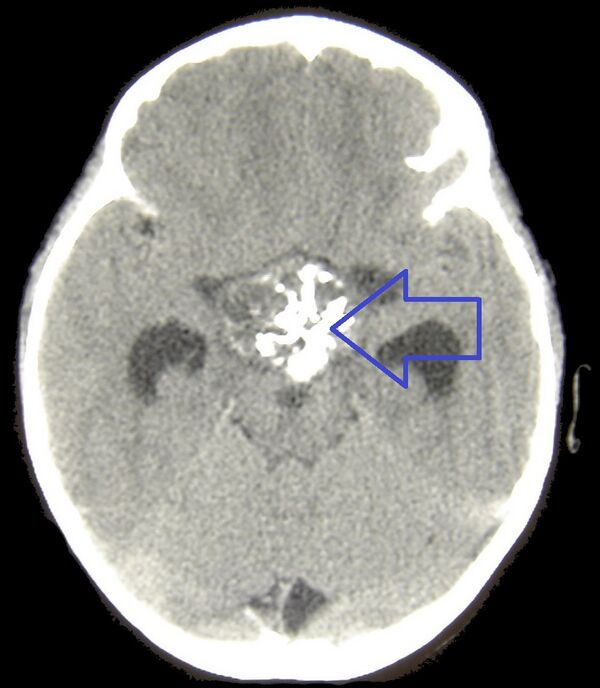

Компьютерная томография головного мозга хорошо выявляет как плотную, так и кистозную части краниофарингиом. Кальцификаты определяются в 95 % случаев у детей и примерно в 50 % у взрослых. Кистозный компонент имеет несколько бо́льшую плотность по сравнению с ликвором, распространяется кпереди и/или латерально и обычно окружает солидный компонент. При введении контрастных веществ яркость узловой части опухоли в половине наблюдений увеличивается на 8—10 единиц Хаунсфилда[32], что встречается в 90 % случаев[33]. Может визуализироваться смещение А1 сегмента передней мозговой артерии или хиазмы зрительного нерва[34].

Магнитно-резонансная томография (МРТ) даёт возможность определить точные размеры краниофарингиом, соотношение их узловой и кистозной частей, размеры и локализацию. Также МРТ даёт представление о состоянии желудочковой системы, наличии или отсутствии гидроцефалии, топографо-анатомическом взаимоотношении опухоли и дна III желудочка[32].